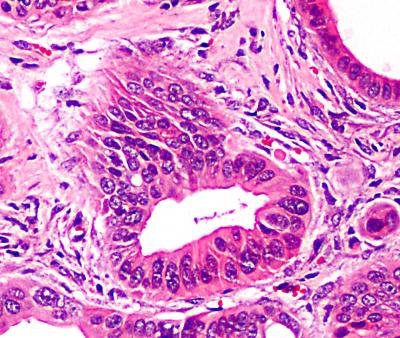

The visual characteristics of these cancer cells -- as they progress from early- to late-stage cancer -- are typical of what is seen in cells analyzed from cancer patients in the clinic now. In the early stage, pancreatic ducts have lesions with cells of an abnormal shape, and express characteristic proteins as measured by stains. Over time, some of these aberrant cells may grow excessively, lose their ductal characteristics, and become invasive.